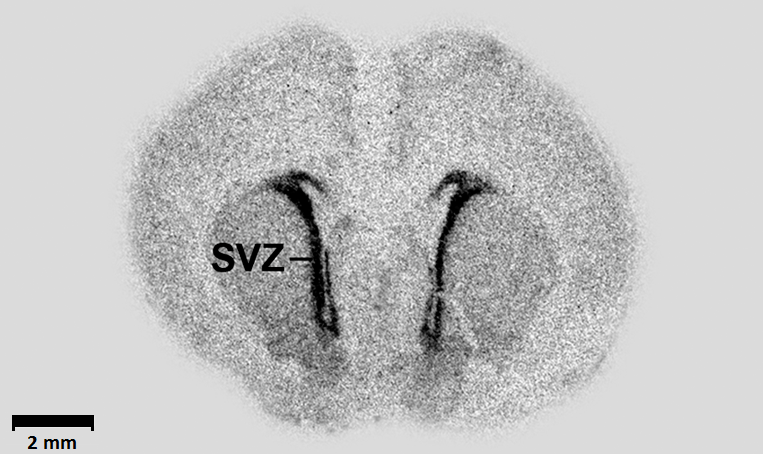

GABA regulates the proliferation of neural progenitor cells,[12][13] the migration[14] and differentiation[15][16] the elongation of neurites[17] and the formation of synapses.[18]

GABA also regulates the growth of embryonic and neural stem cells. GABA can influence the development of neural progenitor cells via brain-derived neurotrophic factor (BDNF) expression.[19] GABA activates the GABAA receptor, causing cell cycle arrest in the S-phase, limiting growth.[20]